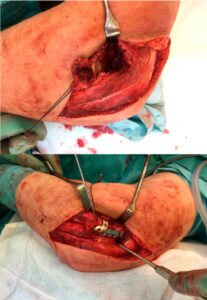

With the patient in a supine position, a posterolateral incision was used. The incision was placed just behind the lateral condyle, extending over the Kocher interval down to the insertion of the collateral ligament complex on the ulna. The fascia over the Kocher interval was incised and followed proximally immediately posterior to the lateral column, releasing the triceps from humerus.

The fractured lateral condyle was mobilized together with the attached ligaments and extensor muscles. The intraarticular fragments were reduced and temporarily fixed with K-wires. Because the coronal shear fragments were thick, fixation from posterior was decided in order not to disturb the articular surfaces. A posterolateral plate with a lateral flange was therefore used.

Approach without jeopardizing the radial nerve and allowing both posterior and anterior access.